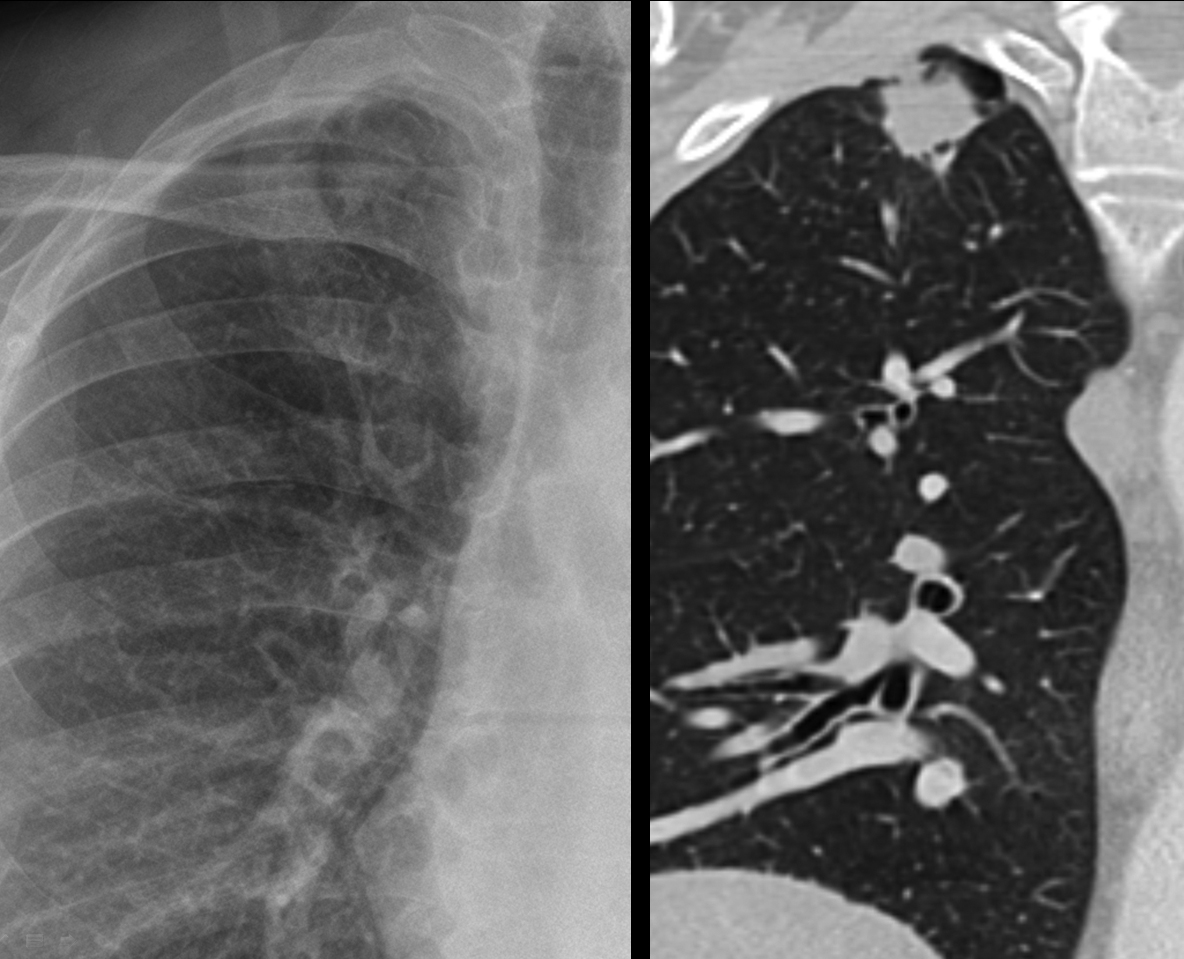

Lung Cancer

Nodules & Masses

Subtle apical cancer